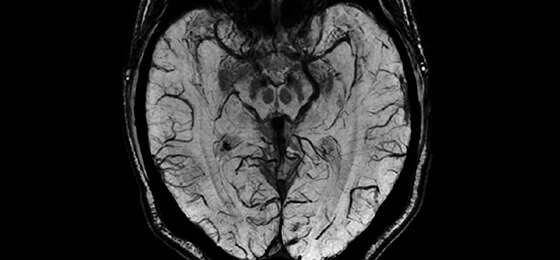

For the first time ever in the industry, you can generate multiple image contrasts in a single MRI scan including T1, T2, STIR, T1 FLAIR, T2 FLAIR* and PD contrasts of the brain in a single acquisition.

One scan that can do the work of many, with images acquired in as little as half the time to acquire separate sequences, fully integrated in a seamless workflow.

You can change the contrast of the image by manipulating TR, TE and TI even after the scan is completed and the patient has exited the MR room. MAGiC processing will provide you any desired contrast paving the way to new diagnostic capabilities.

MAGiC even goes beyond standard MR weighted images by processing raw data into parametric T1, T2 and PD maps.